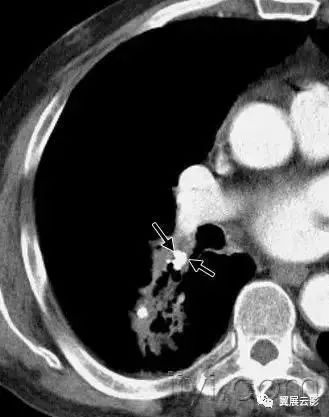

四十、曲菌球

病理:曲菌球是孤立的菌丝相互缠绕形成的肿块,常是曲菌类病原,黏液、纤维素、细胞碎片共同构成空洞成分,常发射跟你在纤维空洞的基础上(例如结核或者结缔组织病)

平片和CT:曲菌球可以随着体位的变化发生变化,部分病例可见空气新月征(图)CT上可以呈现海绵样影像和曲菌球内的钙化灶。同义词是真菌球。